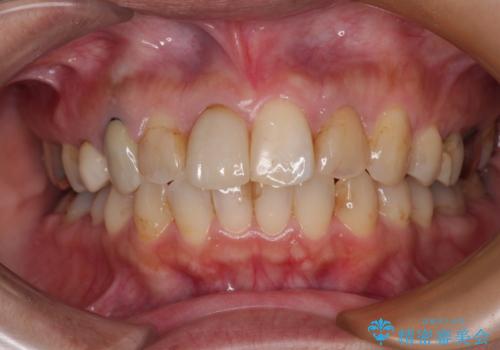

- 上下前歯のデコボコを気にして来院された患者様です。

歯列としては、ワイヤー装置でもインビザラインでも、どちらでも対応可能でしたが、処置されている歯が多く、ワイヤー装置を装着するためには処置歯のやり直しが必要な状態でした。

インビザラインでもアタッチメントを装着できないという同様のデメリットがありますが、比較的矯正治療を行いやすい歯列であったので、インビザラインによる矯正治療を行うこととしました。

術中や仕上がりに特に大きなトラブルはなく、スムーズに治療を終えることができました。